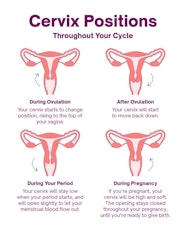

How Can You Tell If Cervix Is Open Or Closed Discount Cfasouthern

https://www.datocms-assets.com/21281/1667313527-cervix-positions-small.jpg

Cervix Before And During Pregnancy